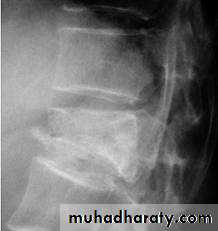

Wedge compression fracture of a vertebral body.

frcature spine and peripheral nerve

Burst fracture of a vertebral body.

WEDGE COMPRESSION FRACTURE

BURST FRACTURE OF A VERTEBRAL BODY

the compression force thus acts vertically in the line of the vertebral bodies.

The intervertebral disc is forced